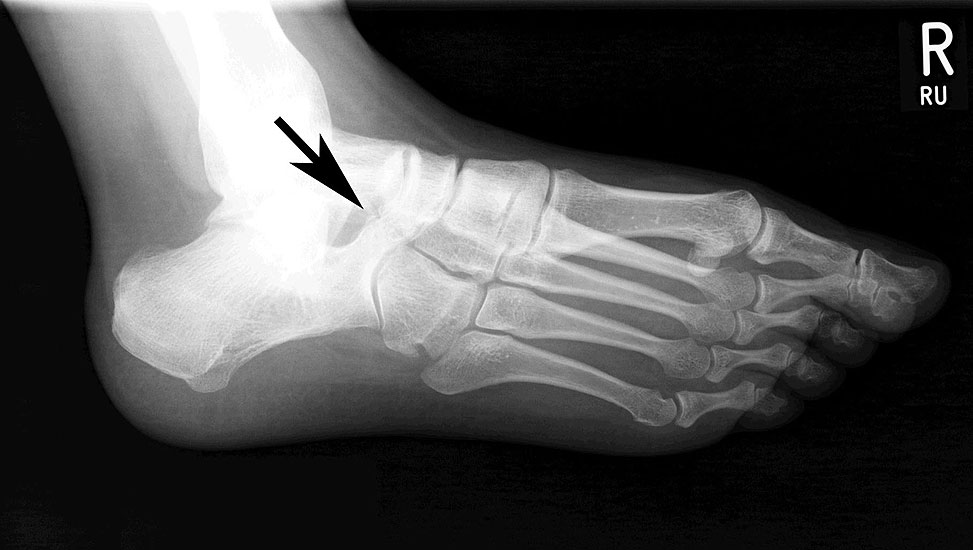

Röntgenbild (Fuß schräg) des Patienten aus Abb. 23 bis 26. Es zeigt sich eine Knochenbrücke zwischen Os naviculare und Calcaneus (Coalitio calcaneonavicularis).

Abbildung 27

Die Befunde aus Abb. 18 bis 21 deuten alle auf eine subtalare Coalitio hin die hier einen Spasmus der Peronealsehnen verursacht. Eine knöcherne Coalitio calcaneonaviculare läßt sich radiologisch meist auf der belasteten Schrägaufnahme des Fußes darstellen.